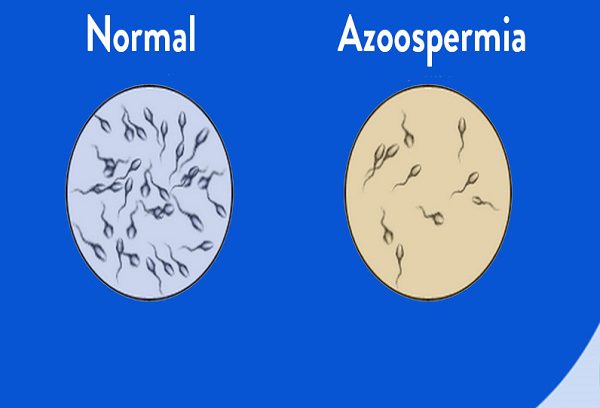

آزواسپرمی و ناباروری

آزواسپرمی و ناباروری به حالتی گفته میشود که در آن اسپرم در مایع منی وجود نداشته باشد.…